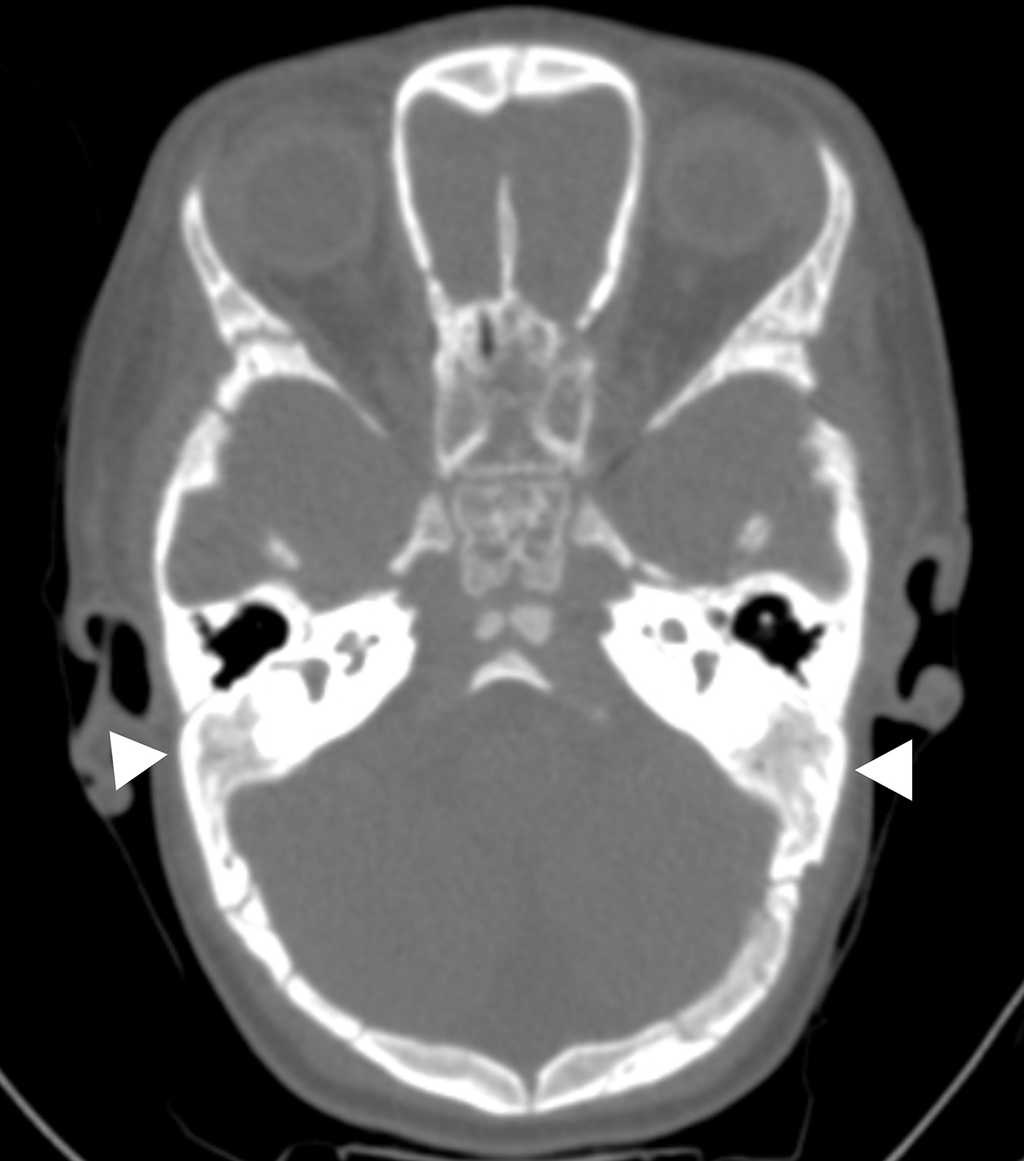

En la tomografía computada (TC) de cráneo se evidenció diastasis de la sutura sagital de las fontanelas anteriores y posteriores, con aumento en el número de los huesos wormianos parietales, temporales y occipitales en ambos lados (fig. 3), más ausencia de neumatización de las celdillas mastoideas (fig. 4).

*Cráneo y columna vertebral

-Diastasis de suturas, fontanelas permeables y presencia de huesos wormianos1,10

-Retraso en la osificación del cráneo

-Neumatización pobre o ausente de los senos frontales, paranasales y mastoideos

-Fusión del estribo a la trompa de Eustaquio y el retrotímpano10